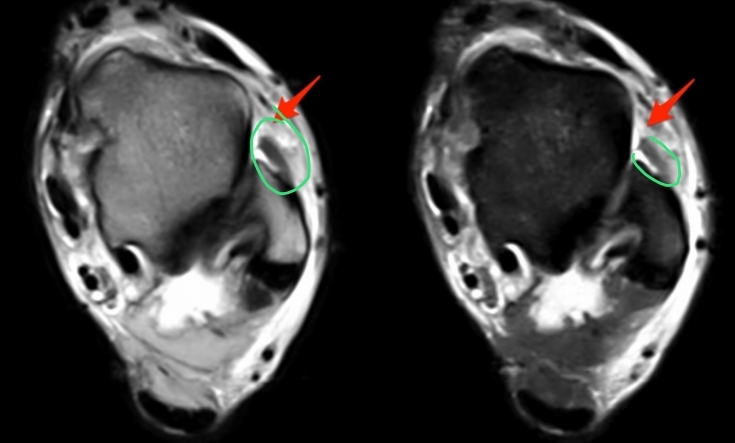

Q

Cuál es el mejor estudio para ver un desgarro meniscal y qué permite ver?

A

RM

- Permite ver y caracterizar desgarros en múltiples planos